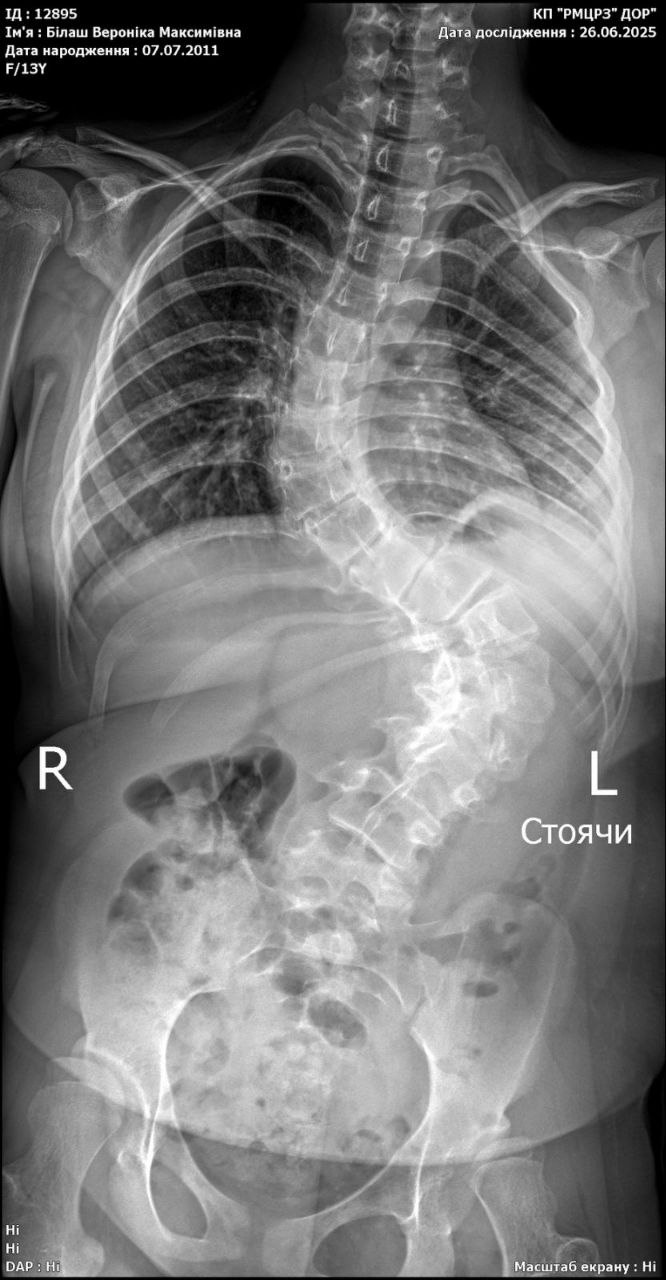

Veronica is our only daughter, who, unfortunately, was born with a serious genetic disease. From that moment on, the struggle began. Ours and our daughter’s. The struggle for every breath, movement and word. But, contrary to negative forecasts, Veronica passed these tests with dignity and made progress in her development. We went to our first kindergarten, and then to a regular school with an inclusive education program. Our daughter delighted us with her successes, but… Our trials did not end there. About 5 years ago, our daughter was diagnosed with another diagnosis - scoliosis of the 2nd degree. According to the doctor’s prescription, Veronica wore a Chenault corset and attended regular exercise classes. But unfortunately, the disease progressed. Currently, she has been diagnosed with scoliosis of the 4th degree, which can only be treated with surgery. Due to her genetic diagnosis, Veronika speaks very poorly, so she cannot say how much it hurts. We can only imagine how difficult it is for our child. Over time, Veronika’s walking became worse and worse and she quickly got tired. She can’t even sit for a long time, now she lies down more. In addition to pain, the diagnosis greatly affects her education, development and quality of life. Doctors at the Rudnev Mother and Child Center recommend surgical intervention to correct scoliotic deformity. For this operation, Veronika needs a metal structure - an implant. Which costs almost 200 thousand hryvnias. We have always tried to cope with our problems on our own, did not turn to anyone for help, but now we are not able to pay for the cost of such treatment on our own. Veronika is a very strong girl, but now she needs your help. Please help! Dinara Salimova, Dnipro. Dmytro Petrenko, Head of the Orthopedics and Traumatology Department of the Rudnev Mother and Child Center (Dnipro): «Veronika has dysplastic thoracolumbar scoliosis of the 4th degree. Recently, the girl’s condition has worsened, the spinal deformity is progressing, the pain in the chest and back has increased, and shortness of breath is increasing. Over time, cardiopulmonary failure will progress. The girl needs to undergo urgent surgical treatment using a metal implant structure. This method is the most suitable for correcting scoliosis. After a period of rehabilitation and adaptation, Veronika will be able to live a full life, forgetting about her illness». The supplier of the metal structure-implant issued an invoice for 193 800 UAH.